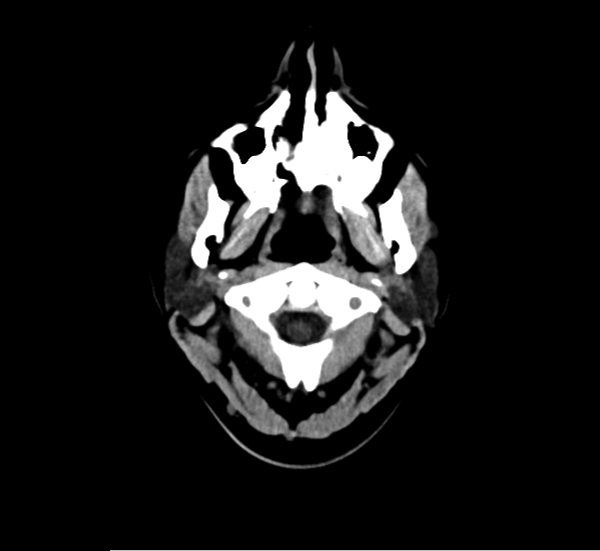

CT Brain Anatomy